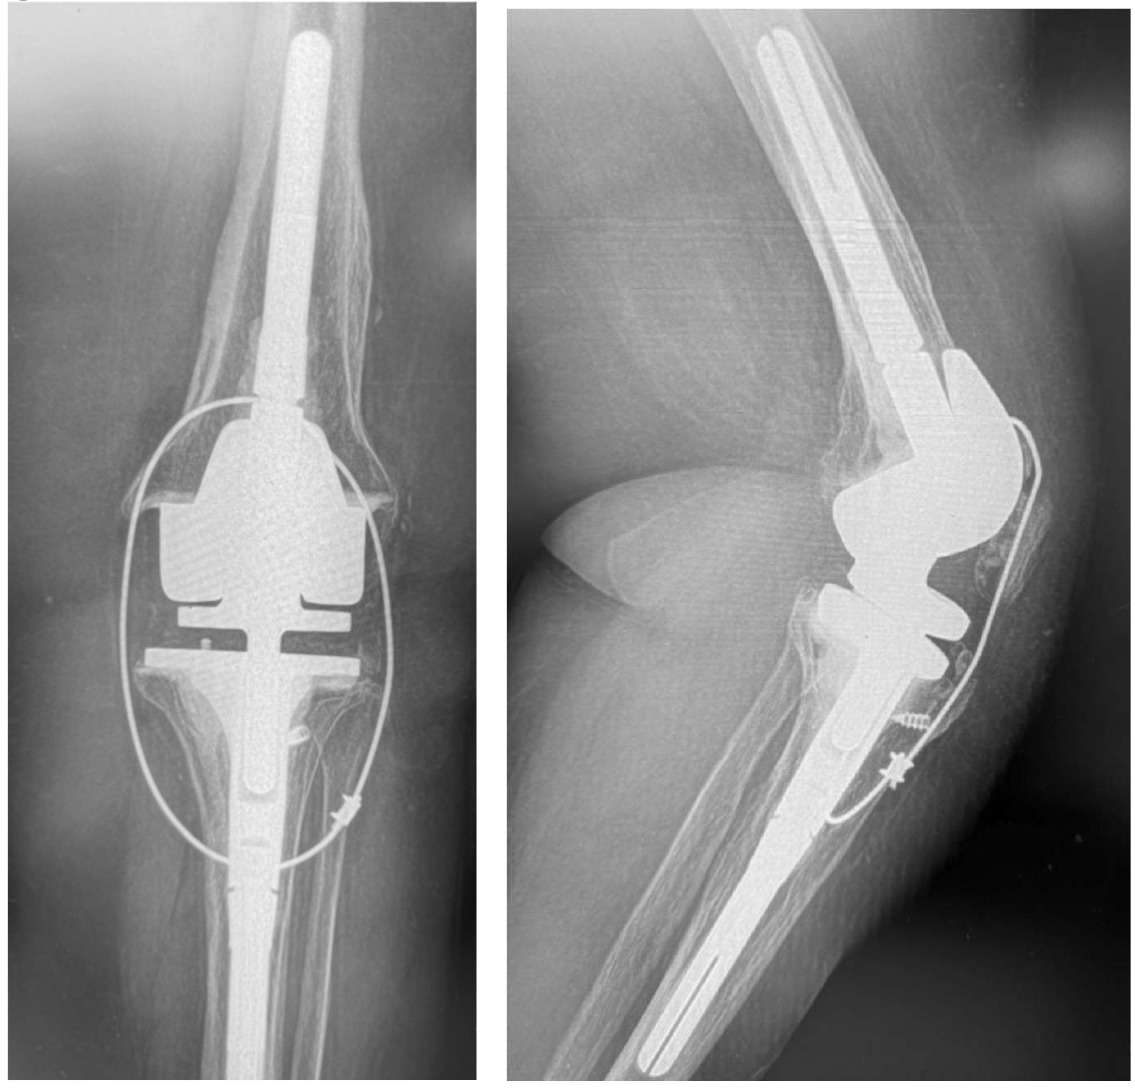

Following extensile exposure of the knee, an anchor suture is placed in the proximal tibia for the primary tendon repair. Next, a hole is drilled below the tibial tubercle through the diaphyseal bone, and the cable is passed through the tibia. Once passed through, the wire is laid within the gutters. (Figure 2) Before the cable is weaved through the quad, feel underneath to avoid passing the cable into the joint. (Figure 3) The cable is then weaved through the quad above the patella. (Figure 4) This technique allows for increased early tensile strength to that quad over time. Then, tighten and crimp the cable (Figures 5 & 6) and you bring the tendon together and then perform the repair. When tightening the cable

But how much do you tighten it? Tighten enough when let go against gravity the knee bends between 30 to 45 degrees. (Figure 7) This will allow good tendon repair protection so that they will stretch the quad out over time, and most of them achieve 90 degrees or more.

We removed the wire about six months following repair. At that time, she had ROM for 0-95 degrees. At six years out following repair she walks with no ambulatory aids and has full extension. (Figures 9, 10A-C)